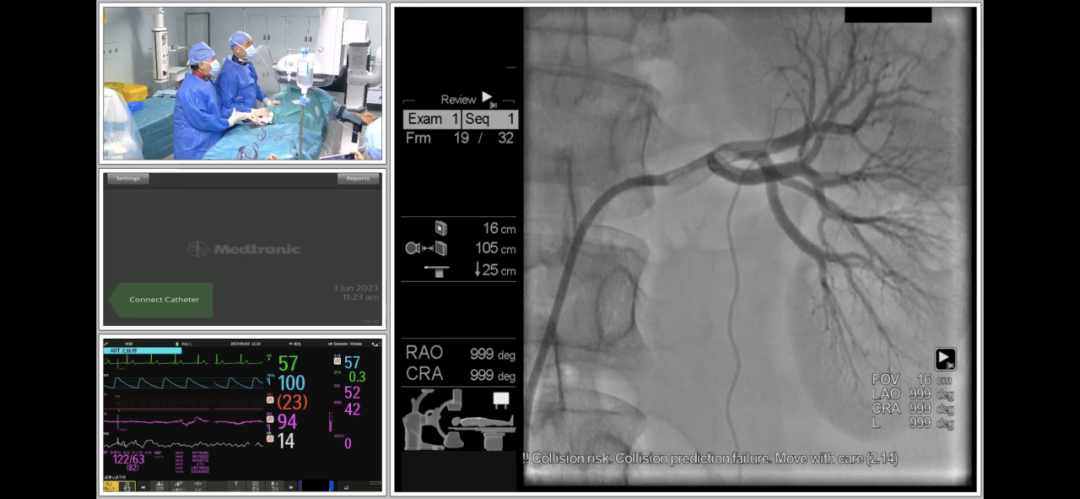

马翔教授和谢翔教授在海南博鳌研究型医院顺利完成RDN手术

术中经股动脉入路,首先对腹主动脉行非选择性造影,以确认肾动脉及副肾动脉开口位置。后通过Launcher导引导管分别对左右肾动脉行选择性造影,在确认血管直径和位置后,决定对分支和主支均进行射频消融治疗。采用由远及近,先分支后主干的消融策略,先后消融了左侧和右侧肾动脉远端分支血管和主干血管,共进行了59个位点的消融,术后造影显示肾动脉血流正常,无痉挛,无狭窄,无明显血管损伤,手术获得圆满成功。